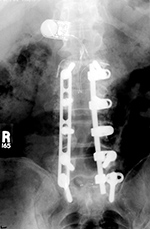

| Shown are pedicle screws and rods on each side, two crosslinks (at L4 and S1), and intervertebral disk spacers at L4-5. |